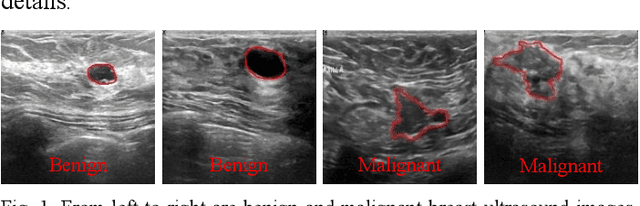

Abstract:Breast cancer is one of the common cancers that endanger the health of women globally. Accurate target lesion segmentation is essential for early clinical intervention and postoperative follow-up. Recently, many convolutional neural networks (CNNs) have been proposed to segment breast tumors from ultrasound images. However, the complex ultrasound pattern and the variable tumor shape and size bring challenges to the accurate segmentation of the breast lesion. Motivated by the selective kernel convolution, we introduce an enhanced selective kernel convolution for breast tumor segmentation, which integrates multiple feature map region representations and adaptively recalibrates the weights of these feature map regions from the channel and spatial dimensions. This region recalibration strategy enables the network to focus more on high-contributing region features and mitigate the perturbation of less useful regions. Finally, the enhanced selective kernel convolution is integrated into U-net with deep supervision constraints to adaptively capture the robust representation of breast tumors. Extensive experiments with twelve state-of-the-art deep learning segmentation methods on three public breast ultrasound datasets demonstrate that our method has a more competitive segmentation performance in breast ultrasound images.

Abstract:Breast lesions segmentation is an important step of computer-aided diagnosis system, and it has attracted much attention. However, accurate segmentation of malignant breast lesions is a challenging task due to the effects of heterogeneous structure and similar intensity distributions. In this paper, a novel bidirectional aware guidance network (BAGNet) is proposed to segment the malignant lesion from breast ultrasound images. Specifically, the bidirectional aware guidance network is used to capture the context between global (low-level) and local (high-level) features from the input coarse saliency map. The introduction of the global feature map can reduce the interference of surrounding tissue (background) on the lesion regions. To evaluate the segmentation performance of the network, we compared with several state-of-the-art medical image segmentation methods on the public breast ultrasound dataset using six commonly used evaluation metrics. Extensive experimental results indicate that our method achieves the most competitive segmentation results on malignant breast ultrasound images.

Abstract:Various deep learning methods have been proposed to segment breast lesion from ultrasound images. However, similar intensity distributions, variable tumor morphology and blurred boundaries present challenges for breast lesions segmentation, especially for malignant tumors with irregular shapes. Considering the complexity of ultrasound images, we develop an adaptive attention U-net (AAU-net) to segment breast lesions automatically and stably from ultrasound images. Specifically, we introduce a hybrid adaptive attention module, which mainly consists of a channel self-attention block and a spatial self-attention block, to replace the traditional convolution operation. Compared with the conventional convolution operation, the design of the hybrid adaptive attention module can help us capture more features under different receptive fields. Different from existing attention mechanisms, the hybrid adaptive attention module can guide the network to adaptively select more robust representation in channel and space dimensions to cope with more complex breast lesions segmentation. Extensive experiments with several state-of-the-art deep learning segmentation methods on three public breast ultrasound datasets show that our method has better performance on breast lesion segmentation. Furthermore, robustness analysis and external experiments demonstrate that our proposed AAU-net has better generalization performance on the segmentation of breast lesions. Moreover, the hybrid adaptive attention module can be flexibly applied to existing network frameworks.